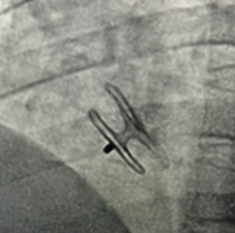

Case 2

卵圆孔未闭合并房间隔膨出瘤伴多孔房缺。卵圆孔隧道长9.0mm,裂隙直径1.0mm。房间隔膨出瘤基底宽12mm,深度约6.0mm,瘤上见两处连续中断,可见左向右分流,分流束宽分别为2.1mm,1.5mm。应用D-shufo 3024-6 PFO封堵器成功封堵。